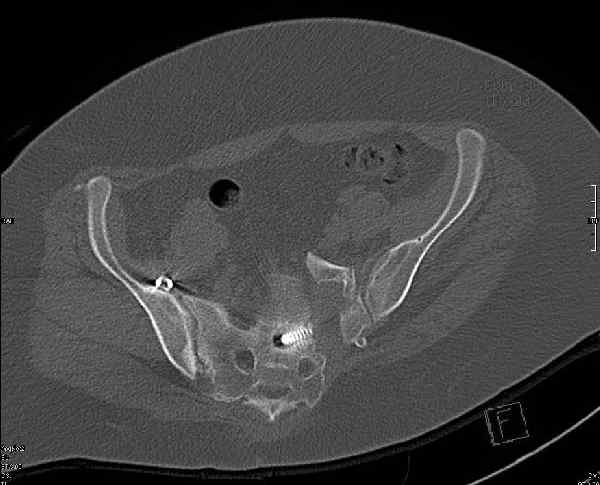

Здравствуйте, коллеги. Какие будут мнения по поводу лечения представляемой больной?

Молодая девушка 19 лет, травма 1 год назад, тогда же прооперирована.

В настоящее время имеются ноющие боли в области крестца слева, нарушение походки, ощущение неуверенности, слабости в левой нижней конечности, неврологически -непостоянные парестезии в левой нижней конечности. Ходит с дополнительной опорой, страдает от ожирения.

Какова по вашему будет оптимальная тактика в отношении несращения крестца? Замена винтов на более длинные с коррекцией их положения+ туннелизация зоны нестращения, открытое вмешательство с костной аутопластикой или еще какие варианты?

В приложении снимки при поступлении и послеоперационные год назад.

Могу сказать одно: миграция винтов и нестабильность синтеза левого подвздошно-крестцовогоо сочленения очевидна.

были использованы винты 7.2 мм, кроме того иетодика транссакральной фиксации не является общепринятой и широко рекомендуемой, но и в этих случаях они наблюдали случаи вторичного смещения